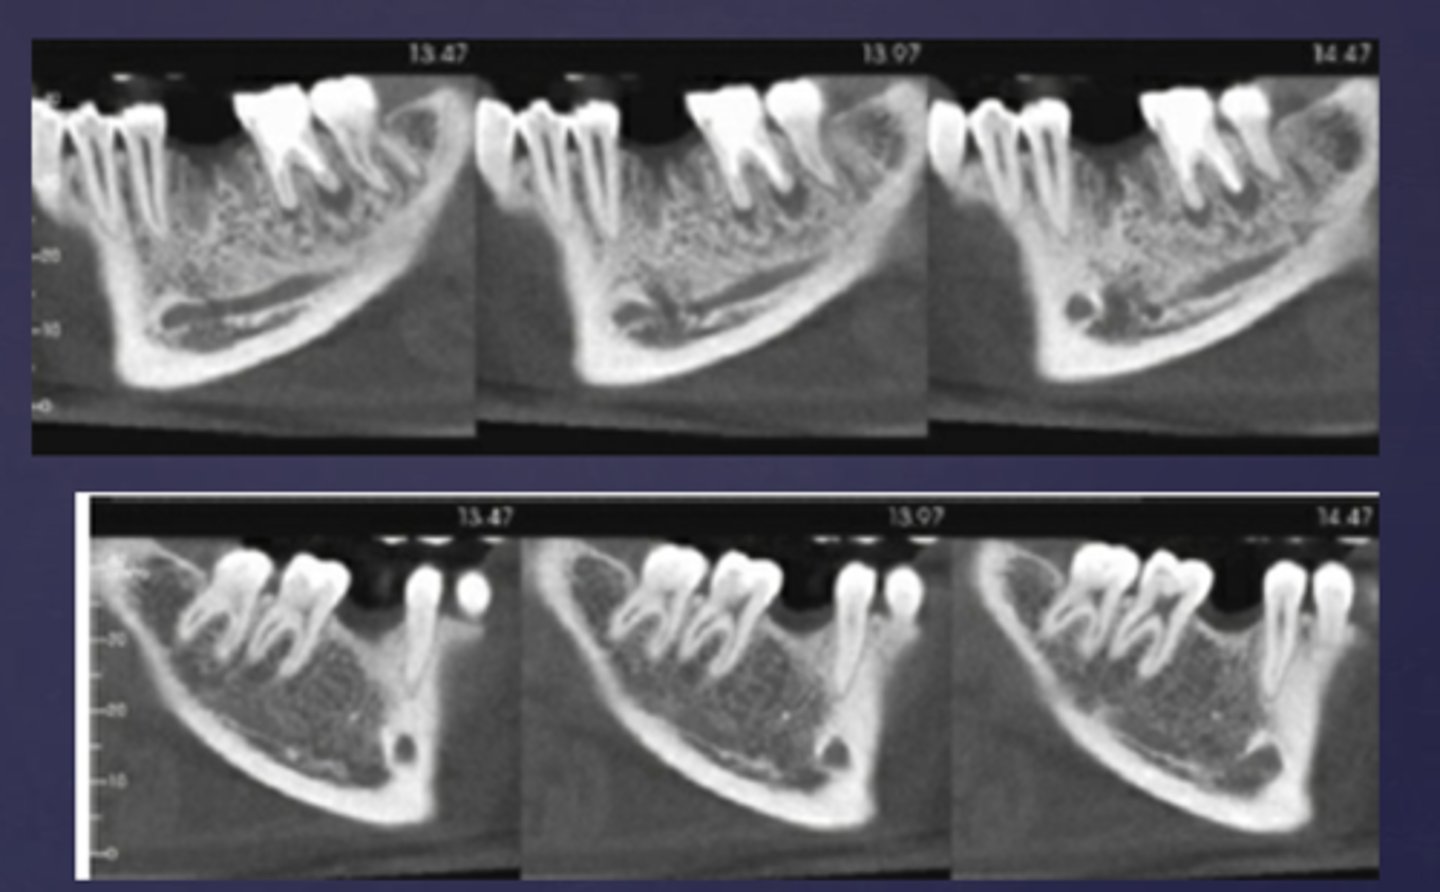

What is the imaging method of choice for osteomyelitis

CBCT

What phase of osteomyelitis does this show?

acute (multiple sequestrae)

sequestrae

What is the black arrow pointing at?

sequestra

What is the white arrow pointing at?